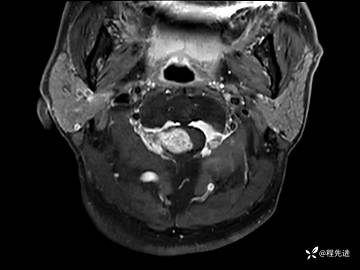

MRI平扫+增强:

T1增强: